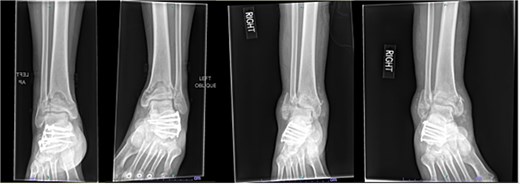

A 38-year-old male with a BMI of 27.5 kg/m2 and a history of alcohol use disorder, paranoid schizophrenia, smoking, and prior bilateral calcaneal fractures treated with ORIF 4 years earlier sustained bilateral pilon fractures after jumping from a third-story window (Fig. 3). He presented to the hospital 5 days after injury.

AP and oblique radiographs of patient 2 obtained after a fall, demonstrating bilateral pilon fractures and retained hardware from prior bilateral calcaneal ORIF.